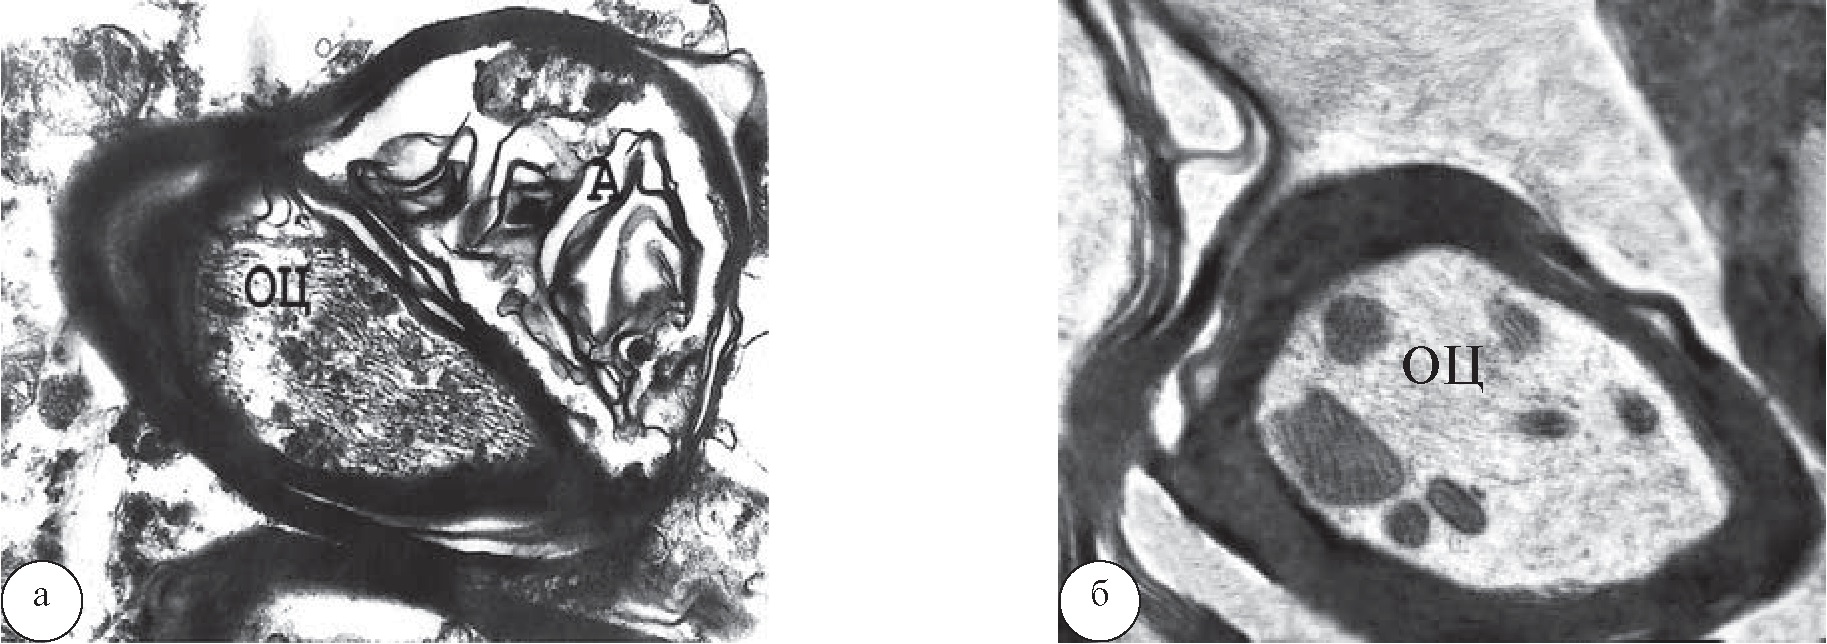

В глиальных клетках СМ у животных КГ после КИН через 1 месяц отмечались значительные изменения в строении ядра и цитоплазмы (рис. 2). У одних астроцитов кариоплазма была так уплотнена, что по своей структуре напоминала кариоплазму олигодендроцитов (ОДЦ), а в других астроцитах она была почти прозрачной. В миелинобразующих ОДЦ ядра были резко и неравномерно осмиофильны, а цитоплазма почти не содержала органелл (рис. 2а). В ряде ОДЦ кариоплазма была просветлена, но хроматин образовывал очень грубые скопления вдоль кариолеммы. В цитоплазме некоторых ОДЦ встречались скопления полисом и измененные органеллы: митохондрии с деформированными кристами и набухшие канальцы ЭПС почти агранулярного вида; кроме того, единичные ОДЦ находились в состоянии некроза (рис. 2б).

Через 1 месяц лечения животных после КИН в СМ одни ОДЦ были нормохромными и имели почти типичную структуру ядра и цитоплазмы (рис. 2в), другие были гиперхромными, отдельные ОДЦ находились в состоянии апоптоза. Среди ОДЦ встречались разделившиеся клетки в телофазе митоза с ядрами неравных размеров и повышенной плотностью кариоплазмы, а также высоким ядерно-цитоплазматическим соотношением, что свидетельствовало об их незрелости. Разделившиеся ОДЦ имели небольшой общий ободок цитоплазмы с многочисленными рибосомами, единичными митохондриями с плотной структурой и лизосомами (рис. 2г).

Рис. 2. ОДЦ поясничного утолщения СМ у крыс КГ: а, б – после КИН СН без лечения; в, г – после лечения с помощью ТКМС: а – ОДЦ со значительным изменением хроматина в ядре (Я) и умеренными изменениями цитоплазмы. Рядом с ним А – миелиновое волокно (МВ) с почти сохранным осевым цилиндром и слабо измененным миелином и Б – МВ с выраженной аксонопатией, ув. ×7000; б – некротизированный ОДЦ и МВ с различной степенью миелино- и аксонопатии (1), ув. ×7000; в – ОДЦ с умеренно гиперхромным ядром (Я) и почти не измененной цитоплазмой, ув. ×8000; г – ОДЦ в телофазе митоза – веретено деления (1), ув. ×8000